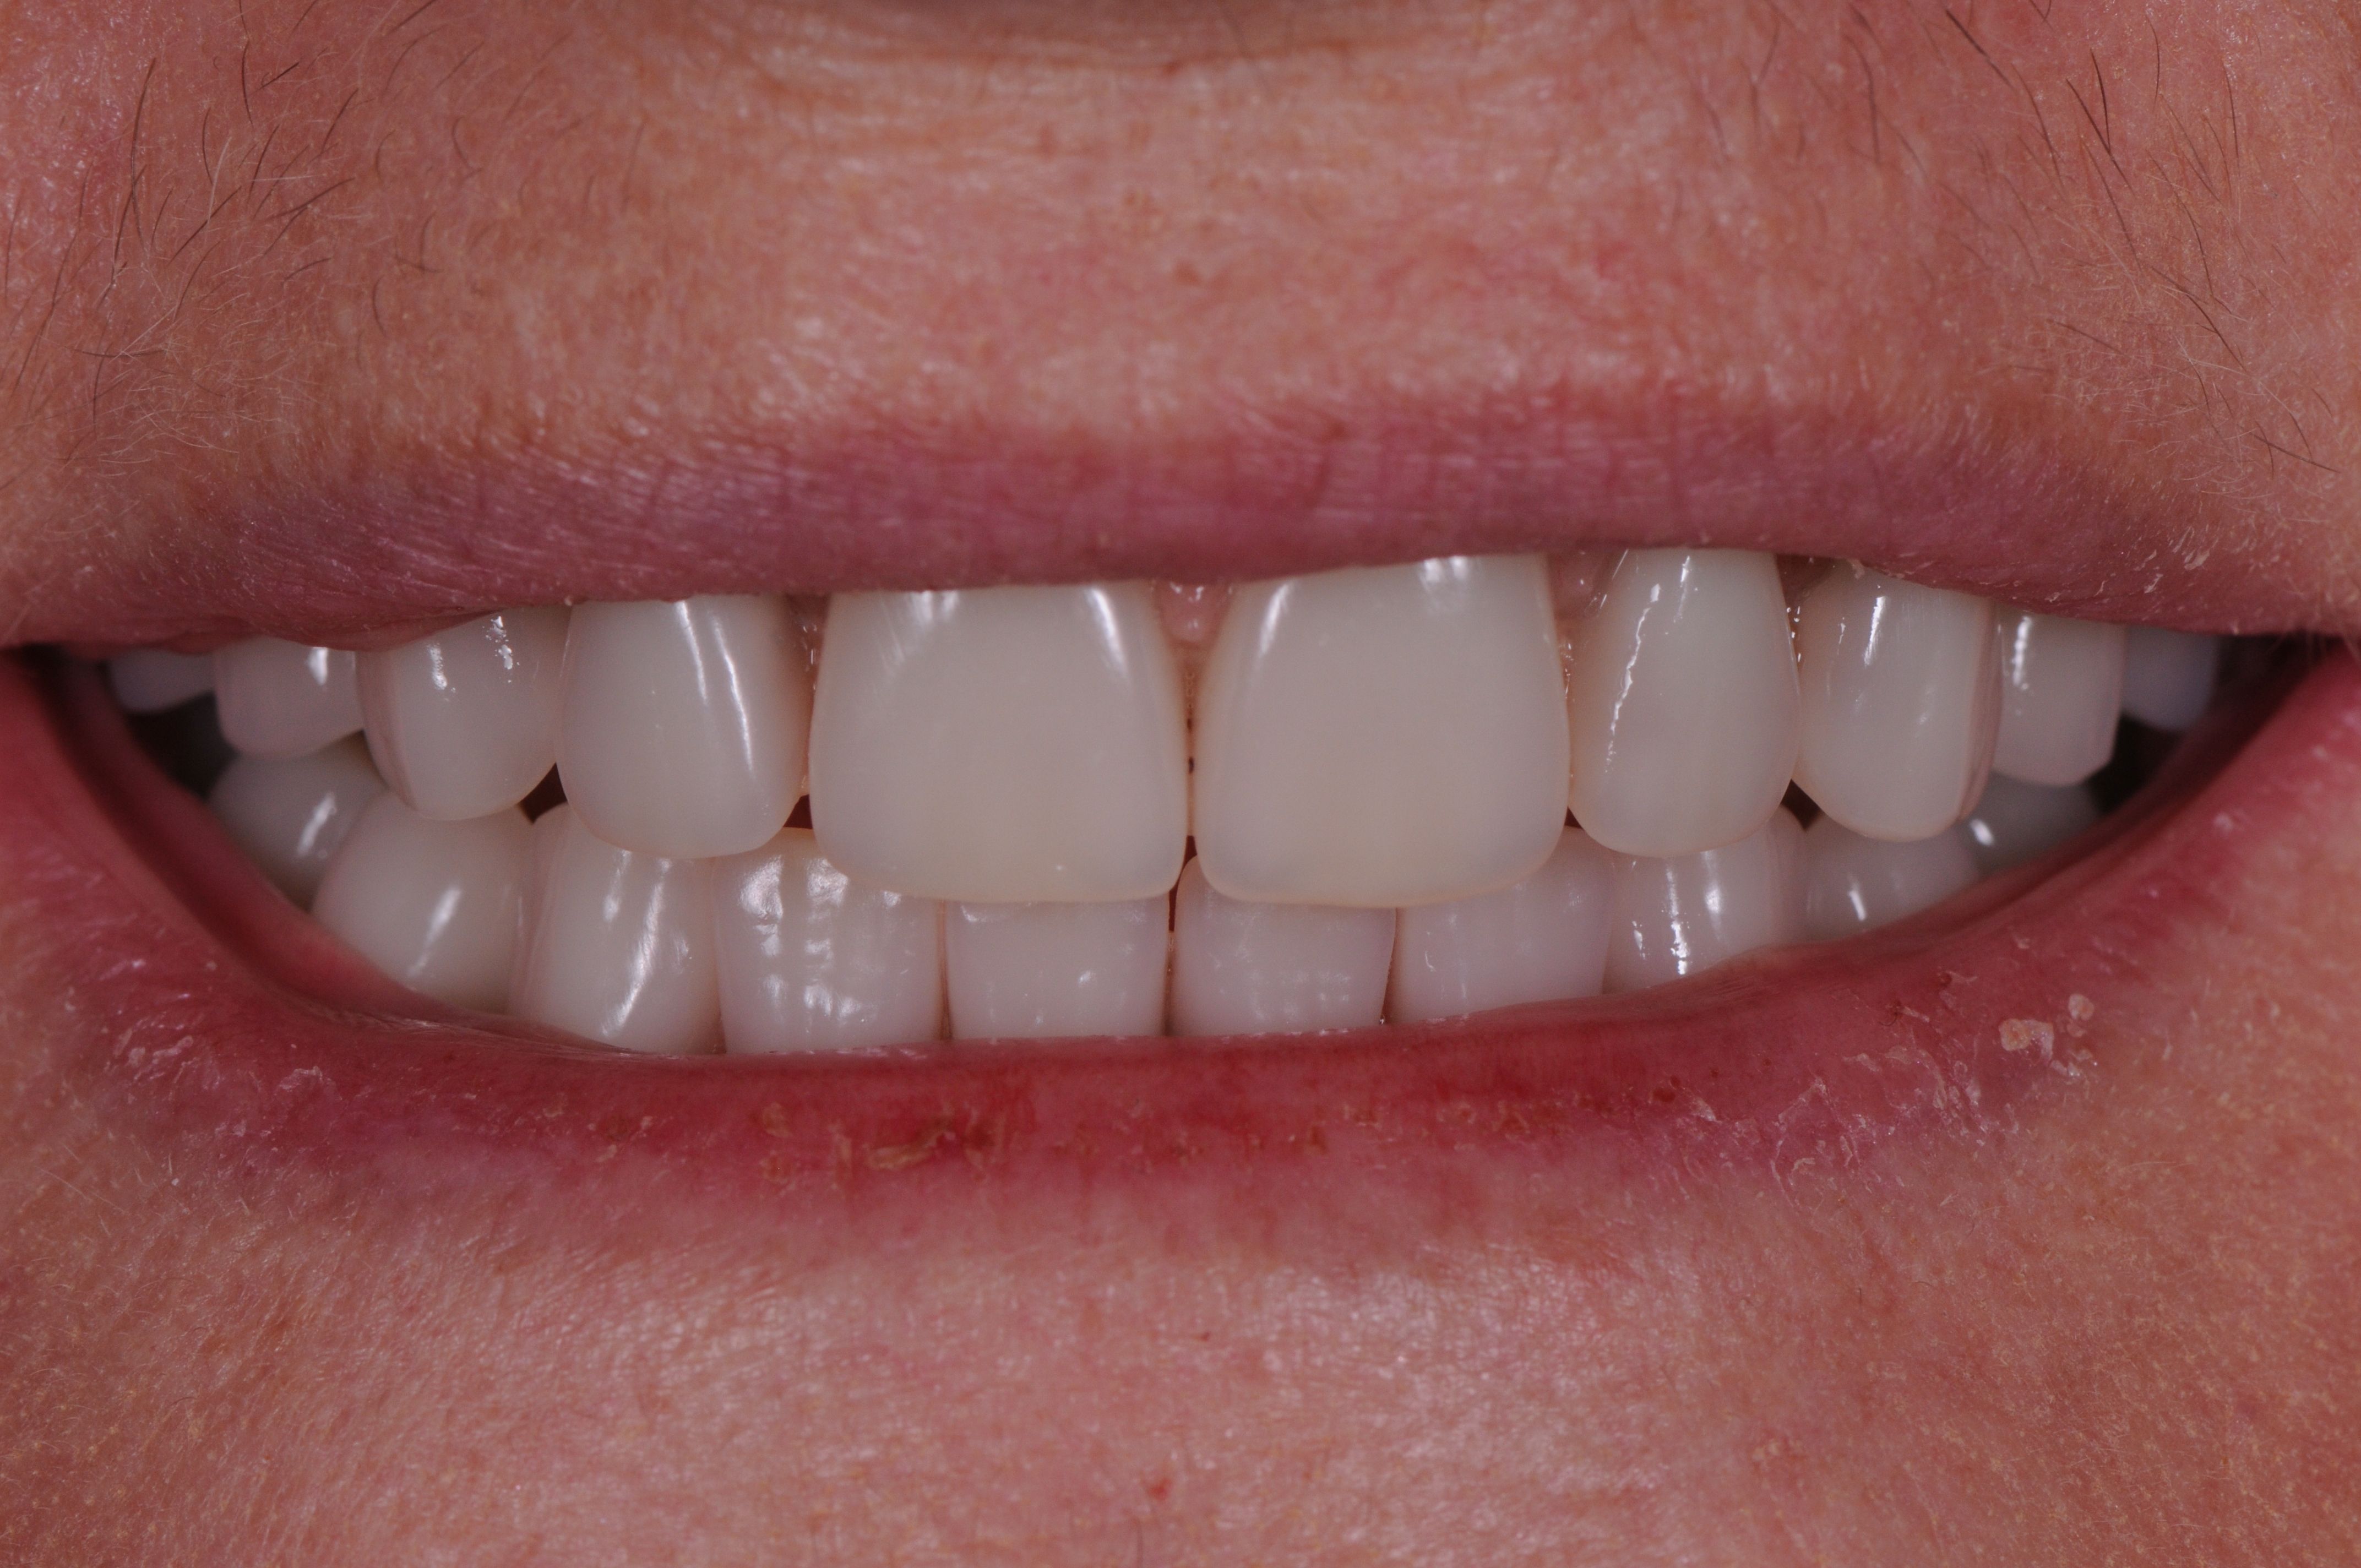

A good, solid bite is achieved with these firmly connected bridges in place. They are comfortable, functional, and secure.

The final bridges create a beautiful aesthetic result too !